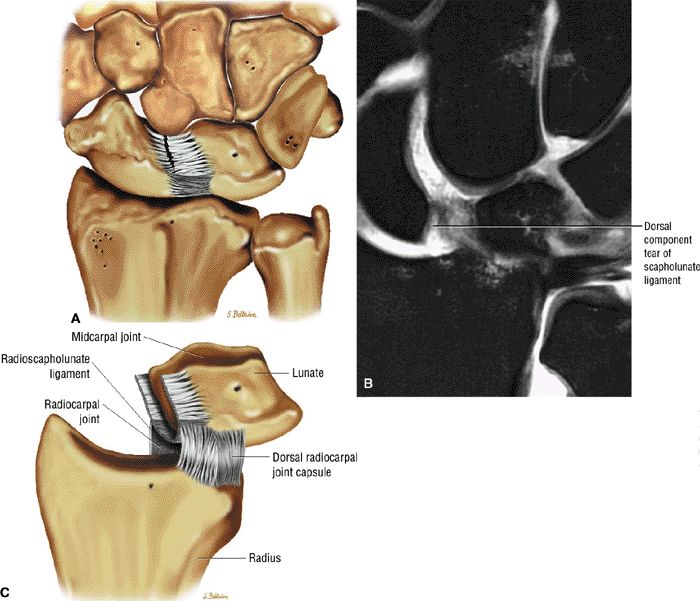

The scapholunate ligament is triangular on coronal section and is peripherally attached at the scapholunate interval. The inner apex of the triangular ligament is not attached to bone and is free within the scapholunate joint (Fig. 10.74).52

The dorsal fibers of the scapholunate ligament are oriented transversely, or perpendicular to the joint, and form a thick bundle. The dorsal portion of the scapho-lunate ligament is considered to be the most important component in maintaining carpal stability.

The membranous scapholunate ligament fibers course peripherally and obliquely from the scaphoid downward to the lunate. The membranous scapholunate ligament fibers attach to both bone and articular cartilage, whereas the dorsal and volar portions of the scapholunate ligament attach directly to bone.

The volar scapholunate ligament fibers course obliquely between the volar aspects of the lunate and scaphoid.

FIGURE 10.73 ● Anatomy of the scapholunate ligament complex on three separate coronal images. (A) Volar component. (B) Membranous component. (C) Dorsal component. (D) On a corresponding axial image all three components of the scapholunate ligament complex are demonstrated. The dorsal scapholunate ligament is horizontally oriented and is perpendicular to the joint. The fibers of the membranous portion of the scapholunate ligament course peripherally and obliquely from the scaphoid downward toward the lunate in a dorsal-to-volar direction. The volar scapholunate ligament courses obliquely from the scaphoid downward to the lunate. This arrangement of scapholunate ligament fibers biomechanically hinges the joint dorsally at the level of the dorsal transverse fibers. In forced extension, scapholunate ligament failure initiates in its volar aspect. S, scaphoid; L, lunate; v, volar component; m, membranous component; d, dorsal component. Arrows correspond to the course of each component of the scapholunate ligament.